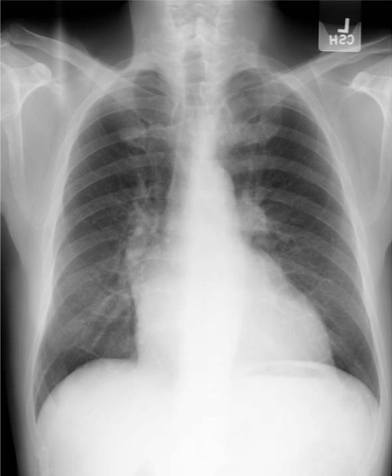

- Cardiomegalia☤ de cavidades izquierdas.

- Edema intersticial☤.

- Patrón venoso en "asta de ciervo"☤.